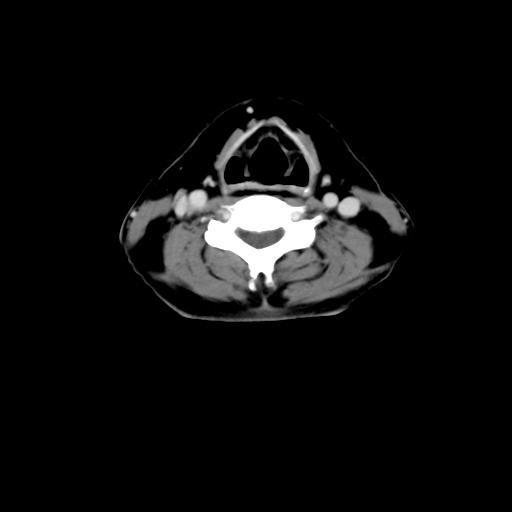

标题: CT24019:男,45岁,发现颈部肿物5个月。 [打印本页]

男,45岁,发现颈部肿物5个月,彩超示:双侧颈部及下颌部软组织增厚。

考虑双侧颈项部良性对称性脂肪增多症。